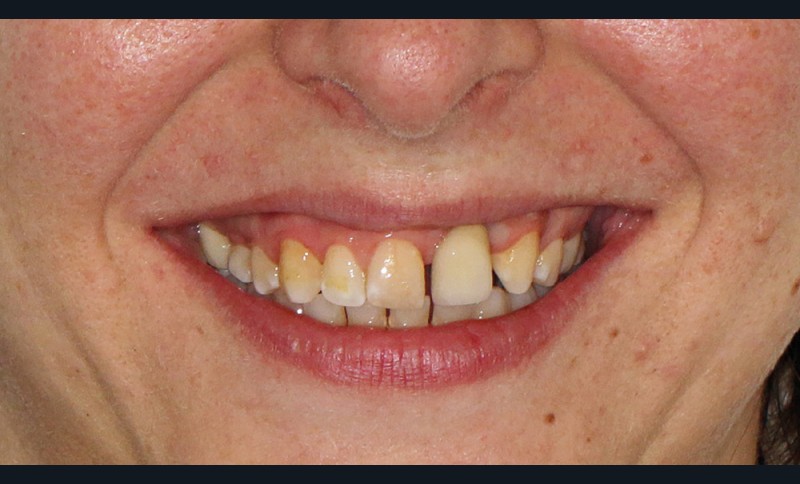

- au niveau esthétique : une couronne sur 21 disgracieuse et une déviation du milieu maxillaire vers la gauche (fig. 2) ;